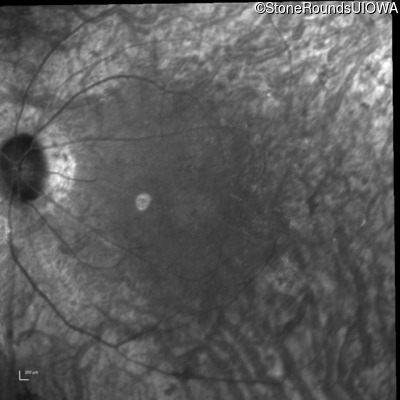

Infrared Fundus Photograph - Left - 20/80 -2

Exemplar